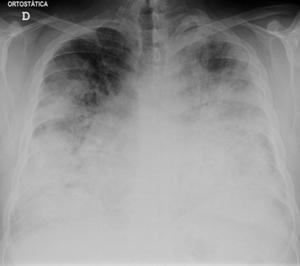

Chest X-ray of a severe case of legionellosis upon admission to the emergency department.

Laboratory tests may show that kidney functions, liver functions, and electrolyte levels are abnormal, which may include low sodium in the blood. Chest X-rays often show pneumonia with consolidation in the bottom portion of both lungs. Distinguishing Legionnaires' disease from other types of pneumonia by symptoms or radiologic findings alone is difficult; other tests are required for definitive diagnosis.